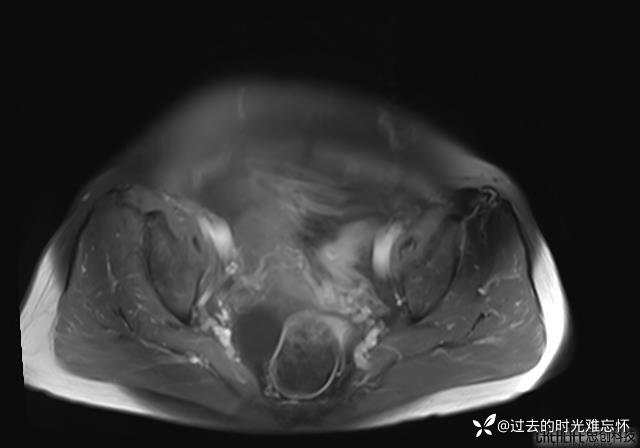

患者性别:女

患者年龄:65岁

主诉: 发现腹部隆起半年余。无其他明显不适。

浆液性囊腺瘤 (22)